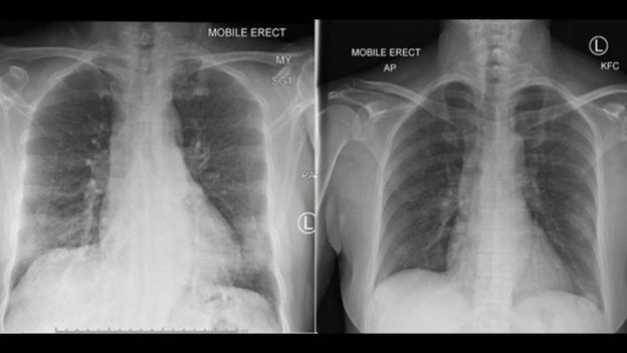

Cum arată plămânii unei paciente cu coronavirus la 5 şi la 10 zile de la infectare FOTO Institutul de Imunologie Doherty din Australia via BBC

Echipa australiană de cercetători şi-a bazat concluziile pe cazul unei paciente care a început să se vindece după cinci zile de la internare fără a i se administra medicamente antivirale, antibiotice sau steroizi. După alte cinci zile plămânii erau curaţi, iar creşteri ale nivelulului anticorpilor contra virusului au fost detectate din ziua 7 până în ziua 20. Pacienta s-a vindecat complet în două săptămâni.

Simptomele sale – letargie, durere de gât, tuse uscată, durere în piept, dispnee uşoară şi senzaţie de febră – au debutat cu 4 zile înainte de prezentarea la spital, se arată în studiul publicat în Nature. Pacienta, o femeie de 47 de ani din Wuhan, China, a fost tratată într-un spital australian timp de 11 zile: s-a vindecat complet în 14 zile.